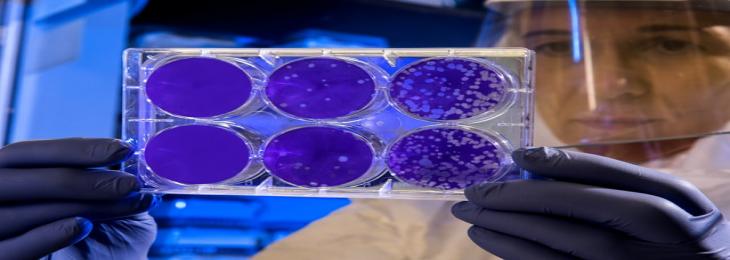

Three bacteria—Ruminococcus, Collinsella, and Bifidobacterium—have been linked to DLB by experts at Nagoya University Graduate Medical School in Japan....